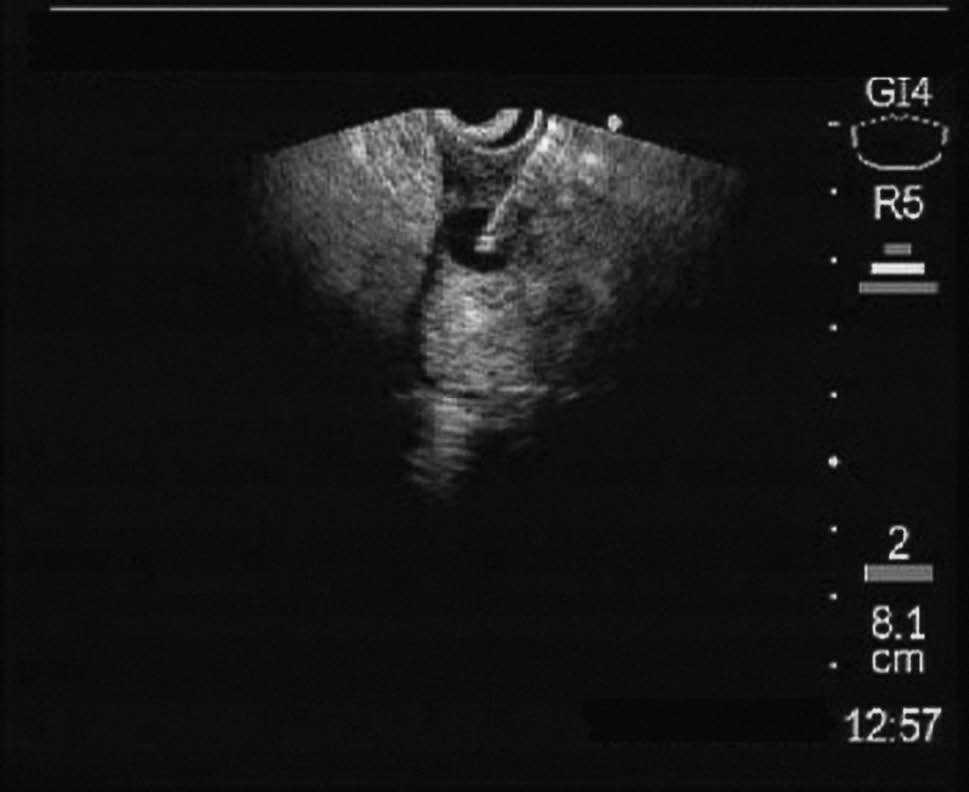

Inicialmente se decidió realizar una endoscopia digestiva alta que puso de manifiesto la existencia de una estenosis en la rodilla duodenal superior con pliegues engrosados, edematosos y congestivos que impedía la progresión del endoscopio. Las biopsias endoscópicas mostraron cambios inflamatorios inespecíficos. En estudios posteriores con ecografía abdominal y tomografía computarizada (TC) se pudo observar un engrosamiento de la pared duodenal y la existencia de lesiones quísticas en la propia pared engrosada (figs. 1 y 2). Para estudiar con detalle la estructura de la pared duodenal, y por la existencia de una estenosis que no permitía la progresión del endoscopio, se decidió realizar una exploración con minisondas ecográficas de 20 MHz, que puso de manifiesto cómo las lesiones quísticas dependían de la tercera capa (submucosa) del segmento duodenal engrosado (fig. 3).

Fig. 3. Exploración de la pared duodenal con minisonda ecográfica de 20 MHz. Lesiones anecoicas de características quísticas dependientes de la tercera capa de la pared duodenal (submucosa).

Una vez efectuado el diagnóstico de distrofia quística de la pared duodenal, decidimos con ecoendoscopio sectorial, previa profilaxis antibiótica, el estudio ecográfico del páncreas y la punción-evacuación del contenido de las lesiones quísticas (fig. 4). Observamos ecográficamente un parénquima pancreático homogéneo sin signos inflamatorios y, al analizar el líquido intraquístico, comprobamos una alta concentración de amilasa (130.000 U/ml). Tras el procedimiento se pudo progresar el endoscopio sin dificultades hasta la segunda porción duodenal y el paciente evolucionó favorablemente con la desaparición de los síntomas y una buena tolerancia a la dieta. En el control ecográfico realizado a las 3 semanas se comprobó la práctica desaparición de las lesiones quísticas, permaneciendo el paciente asintomático trascurridos 7 meses del procedimiento endoscópico.